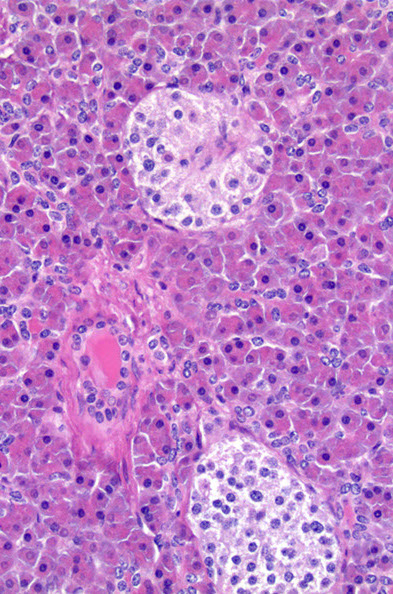

Pancreatic Endocrine Neoplasms (PEN)

- aka Pancreatic Neuroendocrine Tumors (PanNET)

- sometimes called pancreatic islet cell tumors

- 1-2% of pancreatic tumors [1]

Most occur with MEN, tuberous sclerosis, vHL or NF1

- usually are in the tail (where most of the islets are), looking pink and maybe like a big lymph node

- 1/2 are secretory

Insulinoma: 3/4 of PanNET, B-cells, MEN1, clinical triad (?), benign and solitary

Gastrinoma: ~1/4 of PanNETs, MEN1, ZE syndrome, up to 90% are malignant

Glucagonoma: perimenopausal women, MEN1, inc plasma glucagon levels

*** 4 D's: DM, Dermatitis (necrolytic migratory erythema), DVT, Depression ***

- > 50% liver mets at presentation

VIPoma: solitary, large, tail of pancreas, severe diarrhea, hypokalemia, achlorhydria

Somatostatinoma: inc plasma somatostatin, DM, cholelithiasis, diarrhea / steatorrhea

*** Sugar, Stone, Steatorrhea = Somatostatin! ***

Malignant, assoc c MEN1

Micro: small nests or trabeculae of cuboidal cells c central nuclei, stippled chromatin, and granular cytoplasm, growing as trabecular, solid, glandular, gyriform (ribbons and festoons) or nondescript forms (and are histologically classified as such)

- highly vascular stroma

- salt n peppa chromatin

Can secrete multiple types of hormone

IHC: (+) CEA / CEACAM1, individual islet markers (glucagon, insulin...), NSE, chromogranin A / B, synaptophysin, opioid peptides, PR, PAX-8, CD56

- neg: vimentin, acinar markers (trypsin, chymotrypsin, PAS/D), CD10 (1/10+), nuclear B-catenin, ER

Px: dependent on Size and Mitotic / Ki67 levels

- most are low grade (well-differentiated and solitary)

Pancreatic endocrine neoplasms (PEN) - tumor on the right pushes the non-neoplastic pancreatic parenchyma on the left of the arrowheads

PanNET